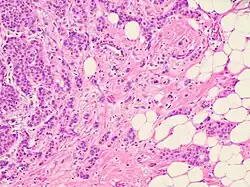

Histopathology of an invasive carcinoma of no special type of the breast. The presence of irregular tumor nests in fatty tissue at right in image confirms the invasive nature.